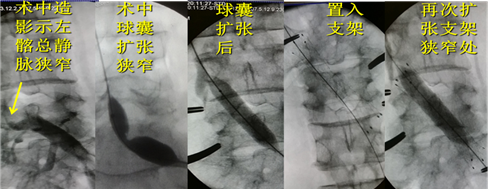

术中图像:

术中主要器材:扩张球囊 12mm*40mm(Bard)血管支架 14mm*60mm(Bard)

术后3天造影:左髂总静脉通畅,支架位置良好,交通支消失